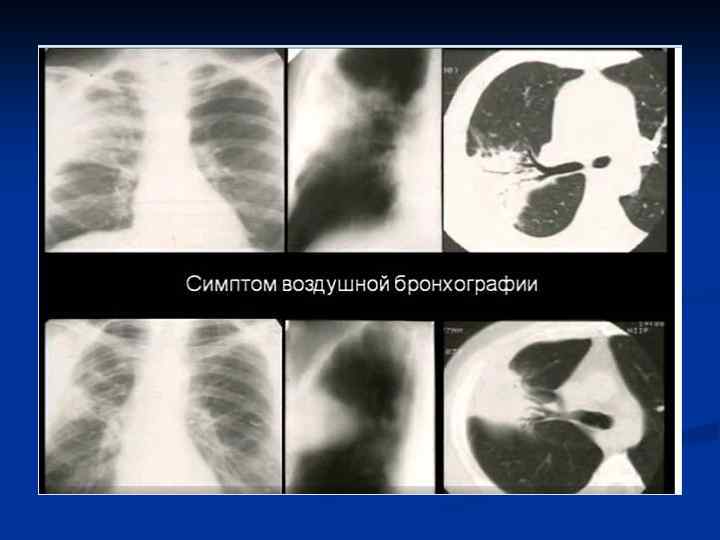

КТ–семиотика плевропневмонии – прямые признаки n n Уплотнение легочной ткани Симптом «воздушной бронхографии» Уменьшение объема Плевральные изменения

Плевропневмония